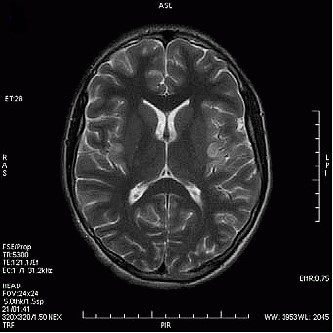

Na obrazie TK zaznaczono zatokę

Ilustracja do pytania 16

A. czołową w przekroju czołowym.

B. czołową w przekroju strzałkowym.

C. szczękową w przekroju strzałkowym.

D. szczękową w przekroju czołowym.